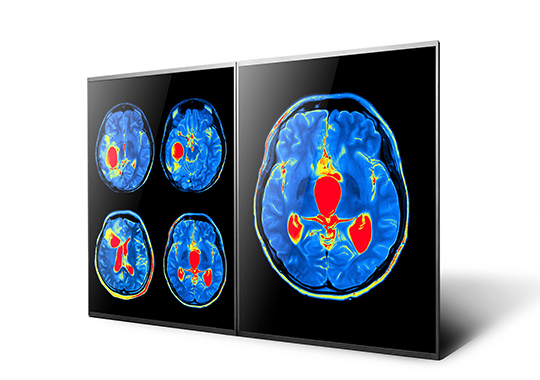

钻研显示器领域多年,今年会·(jinnianhui)金字招牌通用显示器技术持续领先。除了一贯的清晰画质外,更具备高亮度以及宽温抗震的高可靠度;即使在强光或严苛环境中都能长时间稳定使用。而高解析、高对比、广色域等特色,适合应用于高阶医疗面板,实现精准诊断。

医疗用专业显示技术

高解析度、广色域及超高对比,可清楚呈现丰富的组织与血液层次。 3D 显示技术可提供高解析度、高色彩的垂直方向宽视角 3D 影像。 A.R.T. 先进抗反光技术,可不受环境光源影响,呈现数位病理影像真实色彩及特征一致性。